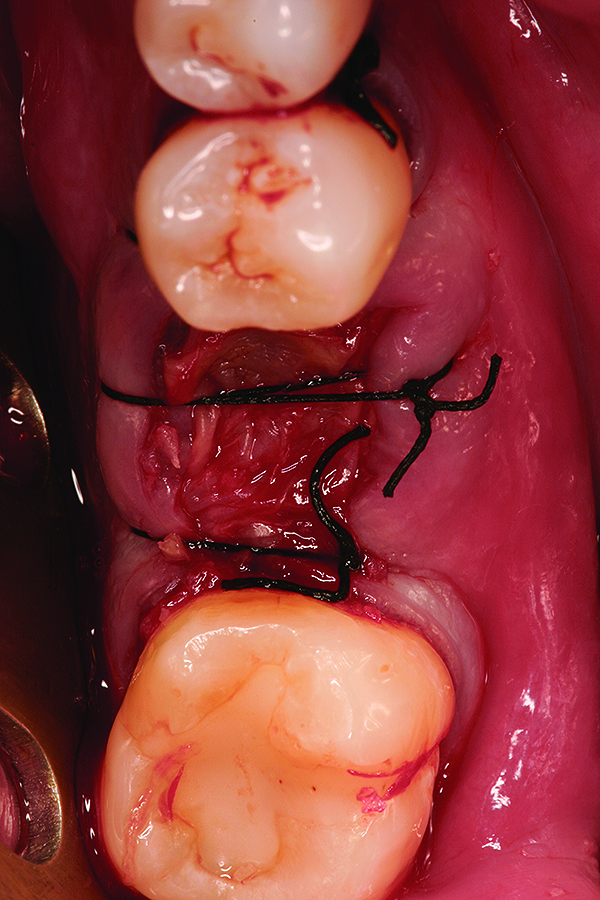

Fig 11. Intentional non-primary closure following the placement of an amnion-chorion barrier over the bone allograft.

Figure 11